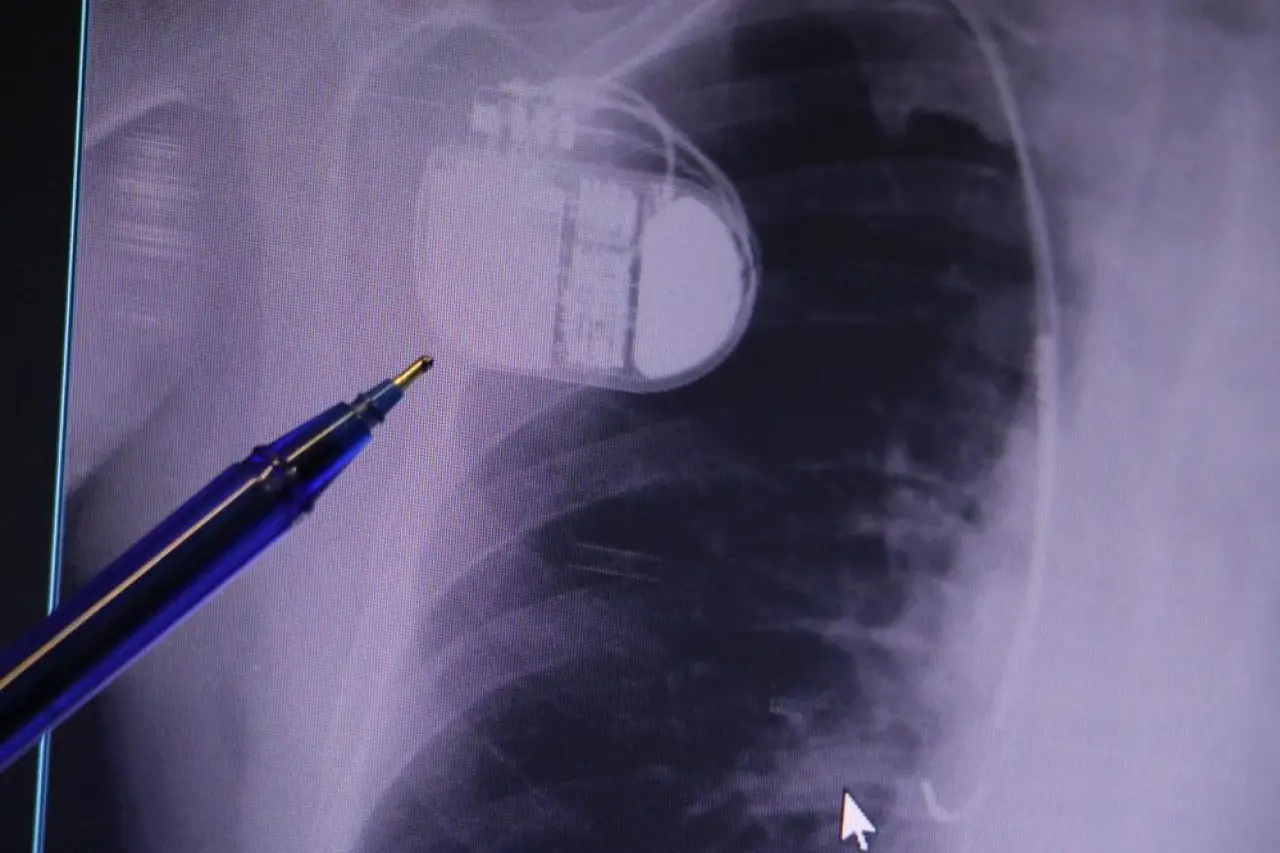

Dr. Erdoğu, kalp krizinden sonra kalp dokularının hasar gördüğünü ve bunun kalp yetersizliği ile ritim bozukluklarına yol açabileceğini belirterek, "Kalp krizinden kurtulmak artık mümkün. Ancak kalp dokusunda meydana gelen hasar uzun vadede ritim bozuklukları ve ani ölümler gibi riskler oluşturabiliyor. Bu nedenle uygun hastalarda kalp pili kullanımı hayat kurtarıcıdır" dedi.

Dr. Erdoğu, son teknoloji kalp pillerinin MR cihazlarına girebildiğini ifade etti. Ancak güvenlik nedeniyle tarama cihazlarından geçilmemesi gerektiğini vurguladı. Erdoğu, "Kalp pilleri bir bilgisayar gibi çalışıyor. Vücuttaki ani titreşimler veya soğuk hava nedeniyle meydana gelen titremeler, kalp pilinin kalbin durduğunu düşünmesine ve yanlış şoklamaya yol açabilir. Bu nedenle hastaların soğuk havalarda daha dikkatli olmasını öneriyoruz" diye konuştu.

Kalp pillerinin ani kalp durmalarında adeta bir yaşam sigortası işlevi gördüğünü belirten Dr. Erdoğu, şunları ekledi: "Pil, hastanın ritmini algılar ve acil durumda gerekli şoklamayı yaparak hayatını kurtarır. Yanında sağlık görevlisi olmayan veya defibrilatörü bulunmayan bir hasta için pil hayati öneme sahiptir. Bu yüzden soğuk havalarda, vücuttaki titremelerden kaynaklanan yanlış şoklamalara karşı temkinli olunmalıdır."

Uzman, kalp hastalığı riskini artıran faktörler arasında yüksek tansiyon ve diyabet gibi kronik hastalıkların da bulunduğunu hatırlatarak, toplumun yaklaşık yüzde 30-35’inin kalp hastalıkları açısından risk altında olduğunu söyledi. Dr. Erdoğu, “Kalp pilinin teknolojik gelişimi son 30 yılda yaşam kalitesini ve hayatta kalma oranını ciddi şekilde artırdı. Uygun endikasyonlarda kullanıldığında ani ölümleri engelleyen en etkili tedavi yöntemlerinden biridir” ifadelerini kullandı.